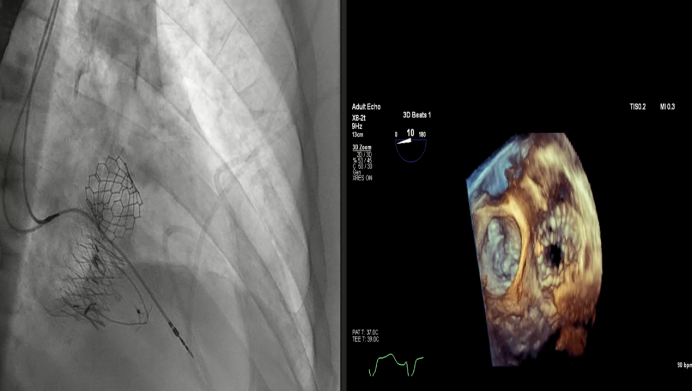

2023年美國心血管研究技術(shù)年度研討會(CRT)在美國華盛頓舉行。作為全球心臟瓣膜介入治療領(lǐng)域的頂級盛會之一,CRT吸引著來自全球瓣膜領(lǐng)域?qū)<覍W(xué)者的目光。在本次大會上,來自法國CHU de Bordeaux的Thomas Modine教授和來自美國Henry Ford Hospital的Dee Dee Wang教授分別報告了關(guān)于通過頸內(nèi)靜脈放置Lux-Valve Plus的早期數(shù)據(jù)和Lux-Valve Plus術(shù)中的超聲指引經(jīng)驗。

Thomas Modine教授公布了早期Lux-Valve Plus篩選病人過程中,由于頸內(nèi)靜脈內(nèi)徑過小或血管扭曲導(dǎo)致不能治療的比例,同時提出通過適當(dāng)?shù)男g(shù)前準(zhǔn)備,有相當(dāng)大一部分病人的頸內(nèi)靜脈可以被擴(kuò)張到足夠Lux-Valve Plus輸送器通過的內(nèi)徑大小。

在早期篩選的病人中,有部分病人的頸內(nèi)靜脈最小直徑小于8.5mm,導(dǎo)致無法接受Lux-Valve Plus治療。然而在之后的臨床實踐中,術(shù)者們發(fā)現(xiàn)通過增加胸腔壓力或心臟前負(fù)荷,頸內(nèi)靜脈可以被擴(kuò)張。如下圖中的病例,術(shù)前的頸部CT顯示頸內(nèi)靜脈最小徑僅為5mm,然而乏式動作(Valsalva maneuver)后血管內(nèi)超聲測得的內(nèi)徑為11mm。這樣的病例提示不能僅僅依靠術(shù)前的頸部CTA來作為唯一的血管入路排除標(biāo)準(zhǔn),通過一些術(shù)前準(zhǔn)備,頸內(nèi)靜脈的內(nèi)徑可以被擴(kuò)張,而血管內(nèi)超聲可以監(jiān)測這一變化。

患者頸內(nèi)靜脈最細(xì)處僅5mm,乏式動作后直徑達(dá)到10.8mm

如果將排除標(biāo)準(zhǔn)從8.5mm調(diào)整為6mm,則僅4.4%的病人會因此而無法接受Lux-Valve Plus的治療。因此,Dr. Modine總結(jié)道,通過頸內(nèi)靜脈的入路是一種安全的方式。同時考慮到頸內(nèi)靜脈與三尖瓣距離更近,角度也相對更平緩,這種入路方式可能對病人來說更加合適。

Dee Dee Wang教授分享了Henry Ford Hospital前4例Lux-Valve Plus的植入經(jīng)驗,并提示術(shù)中確定瓣葉夾持鍵的位置處于三尖瓣瓣環(huán)下方(右心室側(cè)),以及室間隔固定片與室間隔的相對位置關(guān)系是最關(guān)鍵的兩個步驟。使用經(jīng)胃底短軸切面,有時配合右室流入/流出道切面的X-plane就能較容易地獲取相關(guān)影像。由于Lux-Valve Plus對超聲影像的要求較低,手術(shù)過程會相對比較流暢。